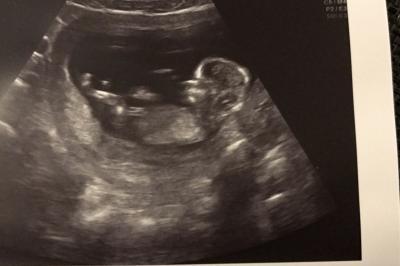

Sooo... alles super! Sie hat doch tatsächlich nochmal geschallt (über den Bauch diesmal), trotz dem super Termin gestern beim Spezialisten.. alles Supi, Herzchen schlägt und Baby hat geschlafen sie hat sogar mal kurz in 3D umgestellt. Da konnte man sehen dass es einen Arm so neben am Kopf hochgestreckt hat. Aber sah ansonsten leider nur aus wie ein kleiner Fleischklops &517; Ansonsten 600g plus bei mir (vom startgewicht aus) und eisenwert an der untersten Grenze und ich muss nun eisentabletten nehmen, aber das kann ich wohl verkraften Nächster Termin dann in 4 langen Wochen am 09.03.

Bild zu Zurück vom fa - Forum für August - Mamis

Süßes Krümelchen

Ein super schönes Bild! Toll :)